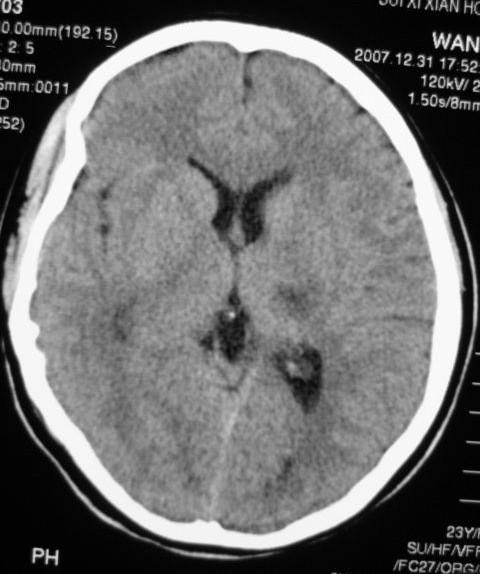

以下是引用zjzjr在2008-2-19 15:45:00的发言:[br]左侧小脑缺血性脑梗塞,基底节区脑梗塞,强烈建议血管造影,除外烟雾病。

以下是引用玉真在2008-2-19 17:46:00的发言:[br]多发性脑梗塞,不知病人是否有风心或先心病史